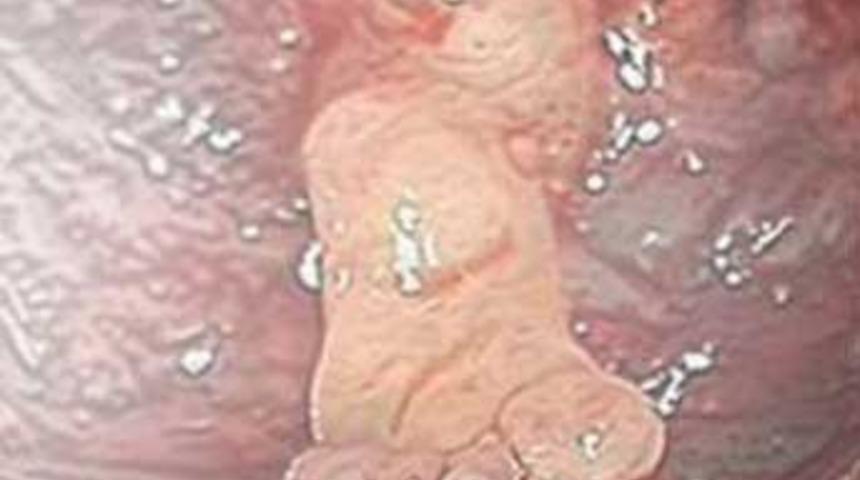

Grabb, Sam'in beynindeki tümörün alındığını, tümörün içindeyse iki küçük ayak, bir el, uyluk kemiği ve bağırsak dokusu bulduklarını söyledi. Grabb, bunun genetik nedenlere bağlı bir beyin tümörü veya fetüs içinde fetüs (FIF) olabileceğini, ancak bunun da çok nadiren beyinde görüldüğünü belirtti. FIF'de, ikiz gebeliklerde bir fetüs diğerinin vücudunun içerisinde bir noktaya kadar gelişip canlılığını yitiriyor ve sadece tek bebek dünyaya geliyor.